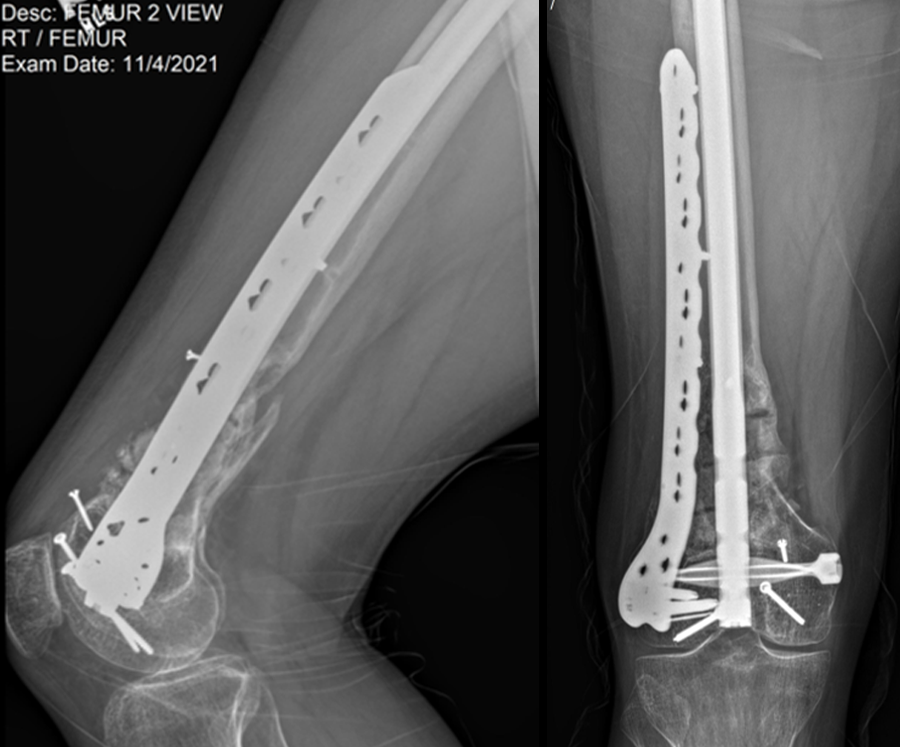

Case 1—Open right supracondylar intracondylar distal femoral fracture following motor vehicle accident

(Case kindly provided by Brent Norris, Orthopedic and Trauma Services of Oklahoma, USA)

A 34-year-old man was involved in a motor vehicle accident in December 2019 and sustained these injuries (Fig 5):

> Left-sided rib fractures with lung contusion

> Open right supracondylar intracondylar distal femoral fracture with possible vascular injury (limb-threatening injury)

> Closed right bimalleolar ankle fracture

> Closed right talar fracture

> Open left plafond fracture

> Open left talar fracture dislocation

> Open left elbow joint

He had no major previous medical history and worked in the furniture delivery business.

At 5 days post-initial surgery, the lung injury was improved, so the patient underwent open reduction and internal fixation (ORIF) of the right distal femur with resection of devitalized bone and cement spacer placement (Fig 7). Definitive fixation of the other fractures (ankle and ribs) was undertaken over time.